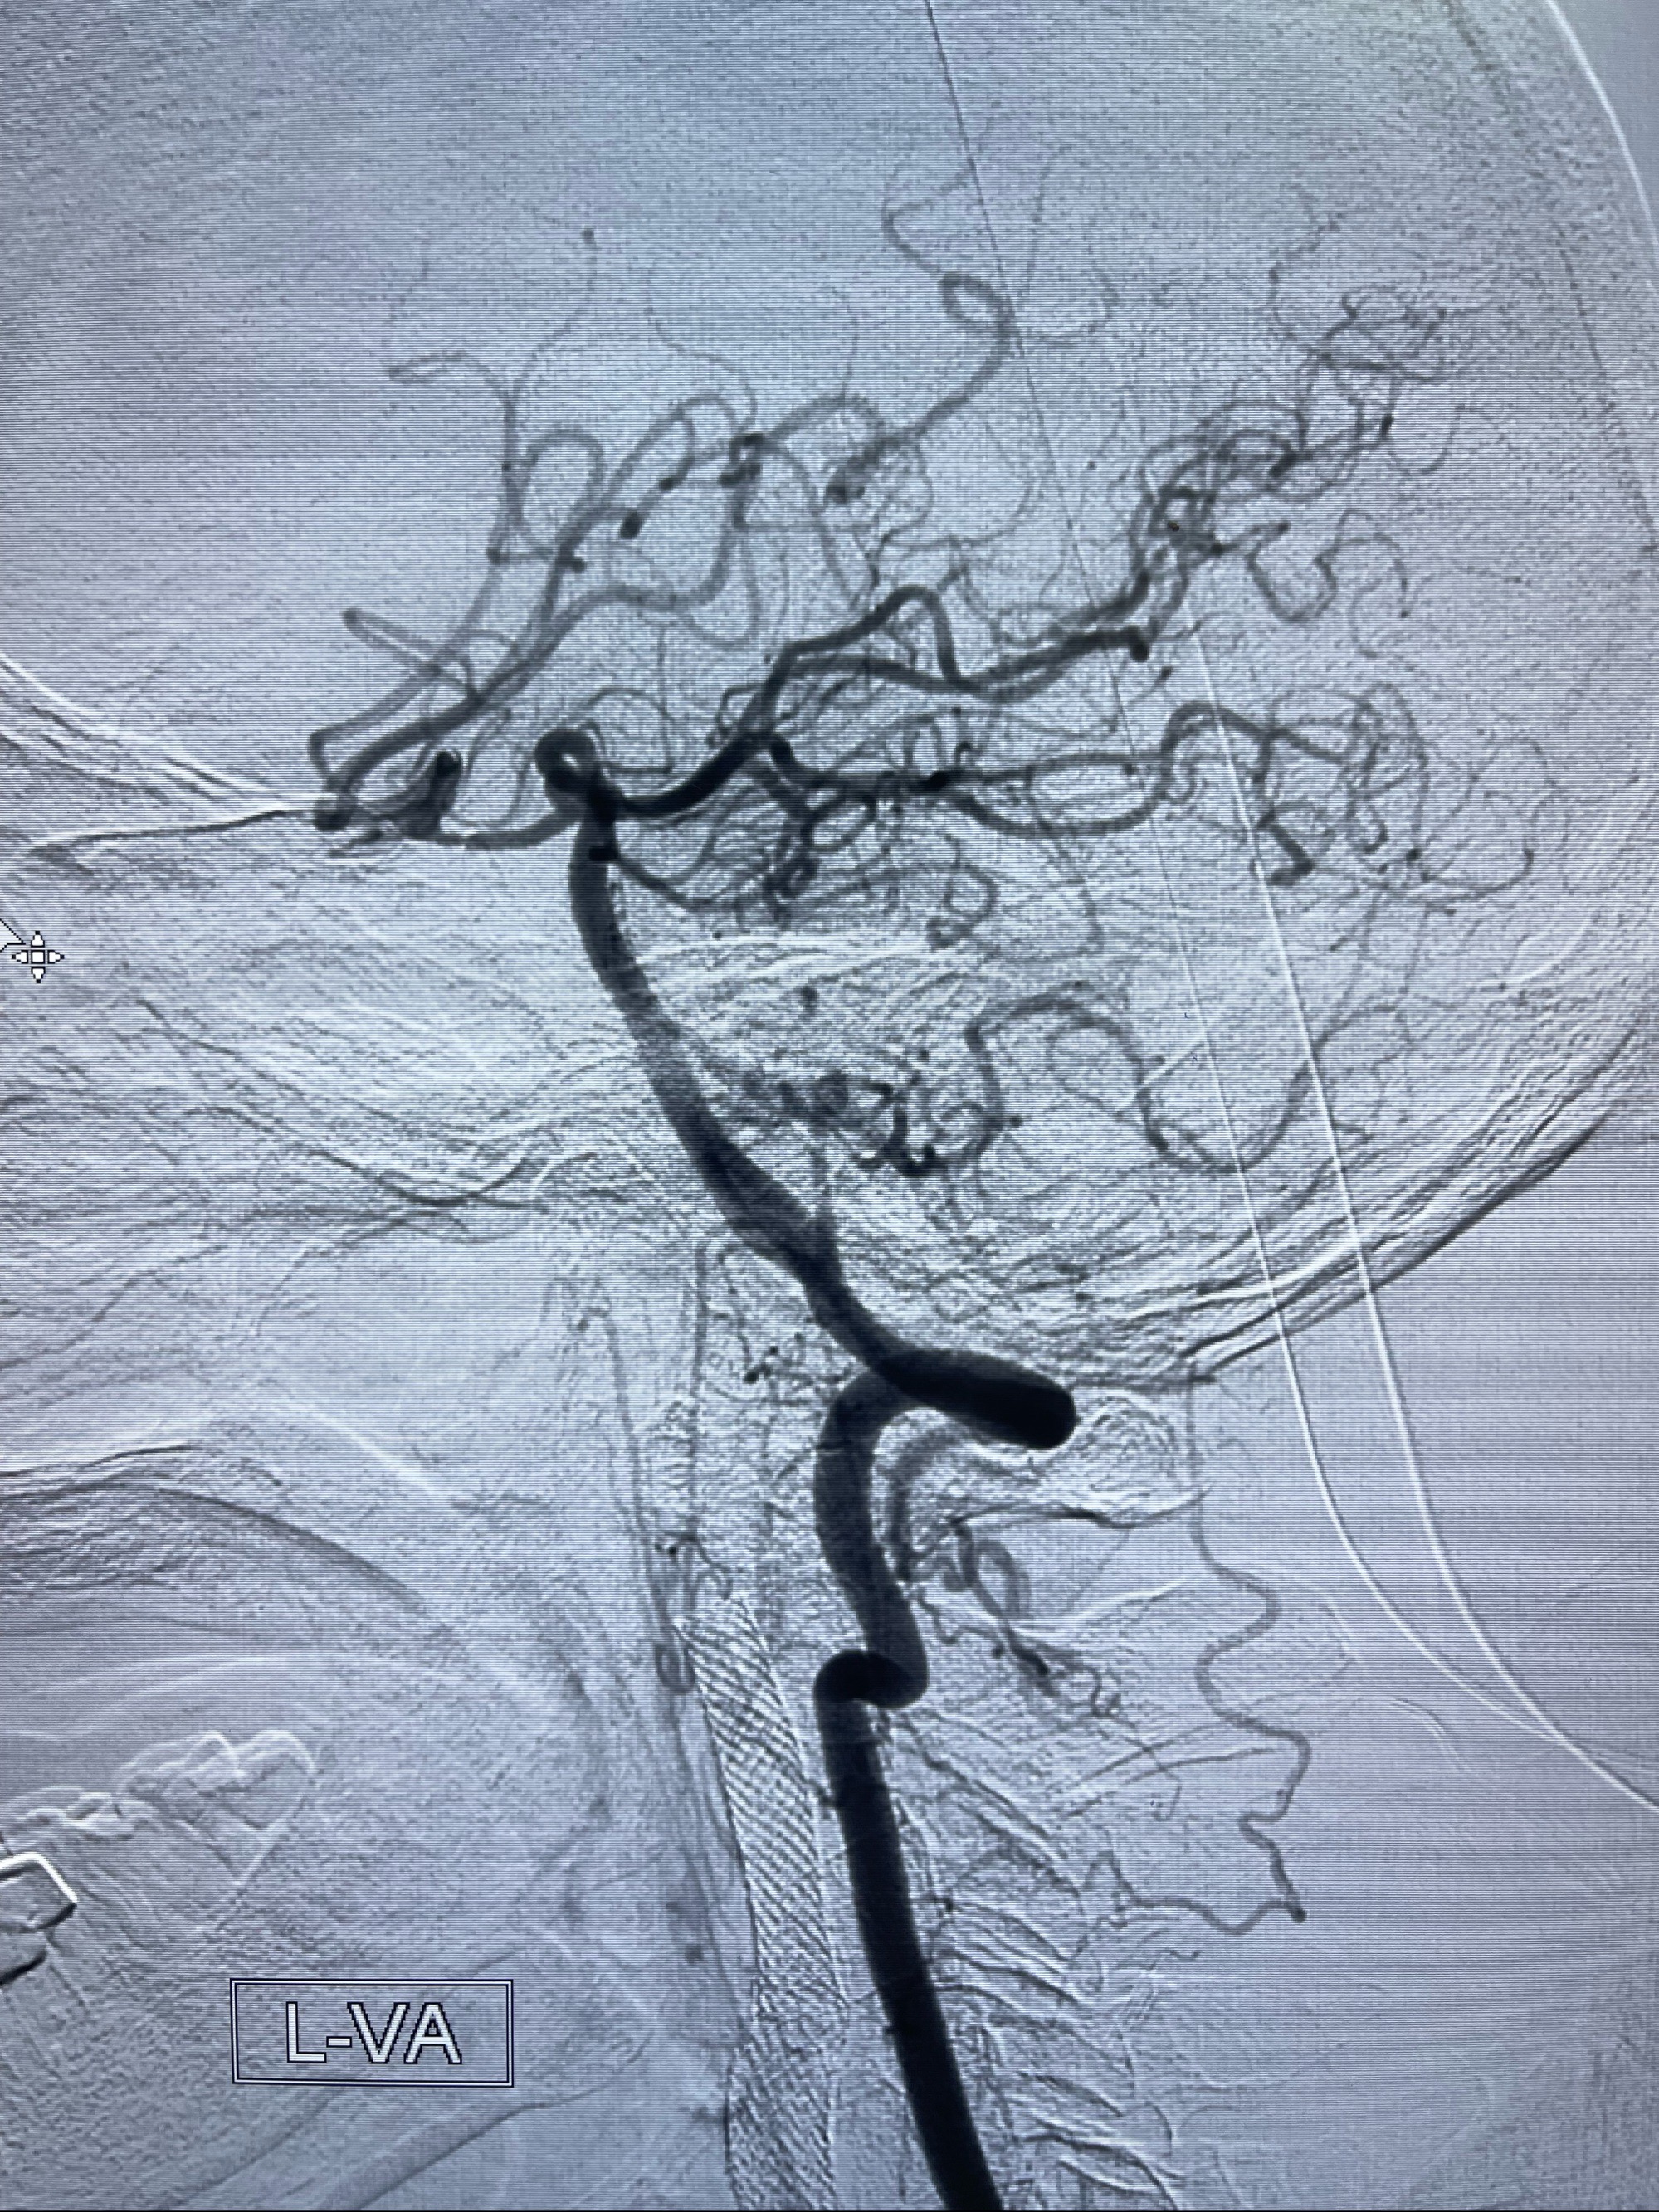

左侧颈总动脉起始段至分叉部闭塞,起始部呈现子弹头样改变

左侧椎动脉可见代偿显示左侧前循环

MRI:显示肿瘤侵犯右侧颈内动脉岩骨段上下,向下至原颈内动脉支架远心段,向上至颅底